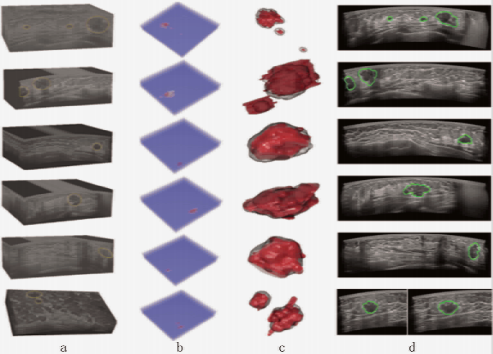

未来乳腺癌筛查趋势应以提升早诊率为导向,将筛查服务下沉到基层,助力提升基层筛查的覆盖率和早诊率。上述人工智能技术是提高基层筛查质量不可或缺的重要手段。同时,针对ABUS设备大、采集阅片时间长等挑战,相关技术发展还应面向仪器小型化、提升传输存储效率等方向。随着仪器小型化、5G网络在乡村的铺开、人工智能技术的成熟,乳腺癌筛查走进乡村将成为可能。凭借高效标准化成像、图像快速传回阅片中心和远程会诊,ABUS有望成为中国乳腺癌筛查的首选技术,见图20。

什么是超声容积探头【解读】自动乳腺容积超声技术专家共识 (2022 版)_https://www.jmylbn.com_新闻资讯_第28张

图20 深圳大学团队基于ABUS影像开发的辅助检测系统结果

a.ABUS数据及乳腺癌区域(黄色标注);b.深度学习辅助检测模型生成的乳腺癌概率图;c.3D显示的乳腺癌标注(红色)及辅助检测结果(灰色);d.ABUS图像上显示的自动检测结果(绿色)。